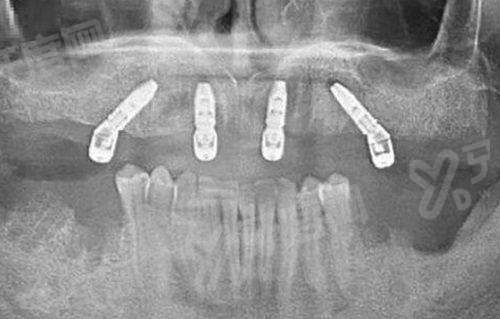

1、进门后护士引导我拍摄了 CBCT 全景片,这台设备能三维重建牙槽骨情况,比传统二维片子看得更清楚,医生能精细判断骨量是否充足。

2、主治医生拿着影像资料,直接在电脑上模拟种植体植入的角度和深度,并没有一味推荐贵的,而是根据我的骨骼条件给出了两种方案供我选择。

1、手术当天,医生使用了动态导航辅助系统,切口非常小,只有几毫米,全程几乎没有出血,这和传统翻瓣手术区别较大。

2、植入种植体时,医生手法特别稳,通过传感器实时反馈扭力值,确保种植体与骨组织结合紧密,整个过程大概只用了二十多分钟。